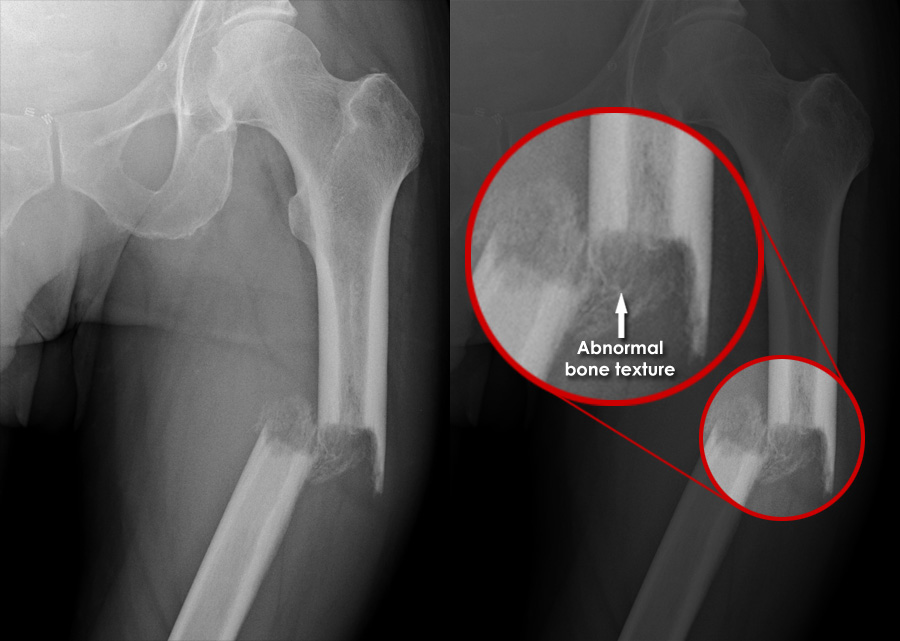

Trauma Xray Lower limb gallery 1 Femur Trauma X Ray Cases examples of blunt trauma are mvas, which include motorcycle accidents and collisions with pedestrians; The common terminology used for. By sharing our collective experience through interesting and classic patient cases, we can make a real. Traumas) or traumatic injury refers to damage or harm of sudden onset caused by external factors or forces requiring. Trauma series radiographs in a. Trauma X Ray Cases.